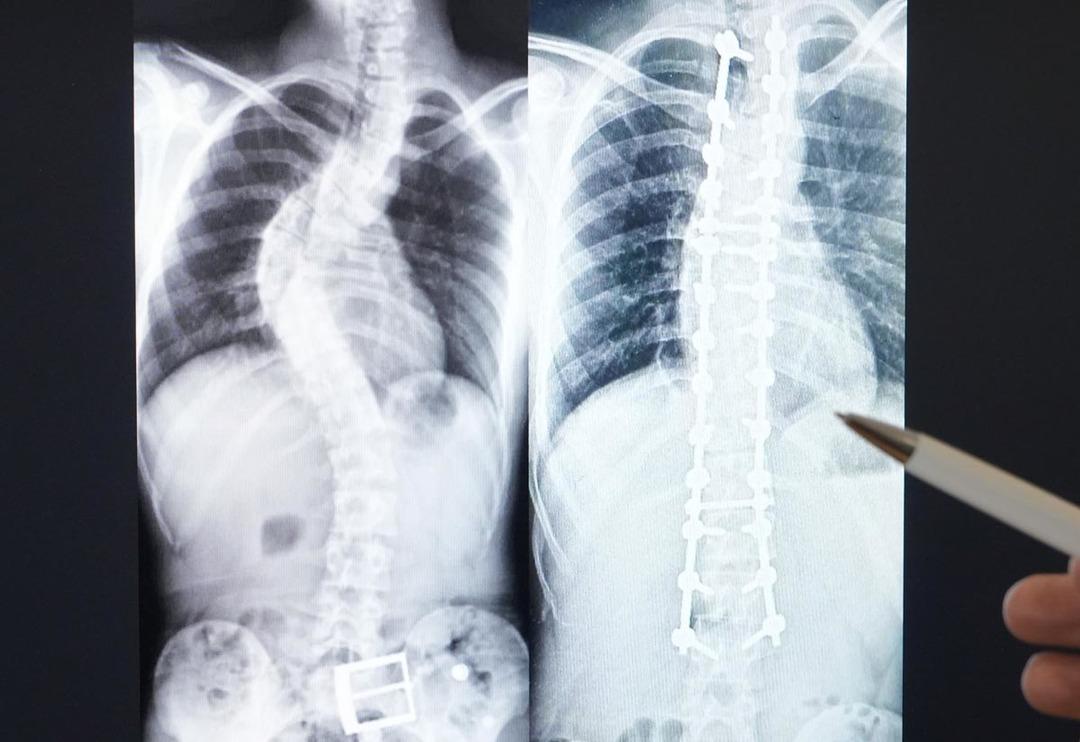

Doç. Dr. Ömer Bozduman, skolyozun önden bakıldığı zaman omurganın eğriliğini ifade ettiğini belirterek, 10 derecenin üstünde çıktığı zaman skolyoz tanımını aldığını ifade etti. Genellikle hastaların duruş bozukluğu şeklinde hastaneye başvurduklarına dile getiren Bozduman, “Çekilen grafilerin de ölçüleri sonucunda belirli derecelerde skolyoz tanımı koyuluyor. Kız çocuklarında daha fazla görülür, doğumsalda olabilir, ileri yaşlarda kırık, enfeksiyon, tümör, kireçlenme gibi durumlarda da meydana gelebilir. Tedavisinde egzersiz, fizik tedavi, korse kullanılır. İleri yaşlarda cerrahi olarak tedavi yapılabilir” ifadelerine yer verdi.

En sık görülenin nedeni tam aydınlatılamayan skolyoz grubu olduğunu dile getiren Bozduman, “Bunlar ergenlik yaşındaki çocuklarda görülen ve cerrahiyle önüne geçilebilecek kısımdır. Anneler babalar ergenlikte çocuklarının mutlaka omuz, kalça dengelerini, belleriyle kolları arasındaki mesafenin simetrik olmasına dikkat etmelidir. Bu aşamada yakaladığımız birçok çocuğu ileride cerrahi ihtiyacı olmadan tedavi ve takip etme şansımız olabiliyor. Biraz daha büyük gruplarda, enfeksiyon, tümör, ramotolojik, sedromik hastalıklar nedeniyle omurgalarda eğrilik olabiliyor. Bazen çok ilerleyip komplikasyonlar oluşturabiliyor. Belirli bir derecenin üzerini ameliyat ediyoruz. Hastaya daha uzun ve kaliteli bir yaşam sağlamak ve derecesinin ilerlemesini engellemektir. Bazen de çok ileri yaşlarda kemik erimesi, kemik kırığı omurga eğriliği olabiliyor. Bunlara kanal darlıkları sinir sıkışması eşlik edebiliyor. Öncelikle kanal darlığı ve sinir sıkışmasını ortadan kaldırıp omurganın eğriliğini düzeltebiliyoruz” diye konuştu.

Bozduman, binde 3 ya da binde 7 arasındaki sıklıkta skolyozun görülebildiğini belirtti. Genelde 10 hastadan birine ameliyat ihtiyacı duyduğunu dile getiren Bozduman, “3’ünü takip, 6’sını fizik tedavi egzersiz korse ile takibe alıyoruz. Temel amacımız burada hataların ameliyat olmadan problemini çözebilmek. Eğer ki ameliyat ihtiyacı olacak şekilde derecesi ilerlediyse değerlendirip, hastanın ihtiyacı olan cerrahiyi fonksiyonlarını kaybetmemek kaydıyla öneriyoruz. Cerrahide hastanın önce bir genel değerlendirmesini yapıyoruz. Hastanın bu cerrahiye uygun olup olmadığına karar veriyoruz. Uygunsa genel anesteziyle açık bir cerrahi uyguluyoruz. Ameliyat sonrası yakın takibe devam ediyoruz. Hastamızı birkaç içinde taburcu ediyoruz ama yine düzenli kontrollerini yapıyoruz” ifadelerine yer verdi. (İHA)